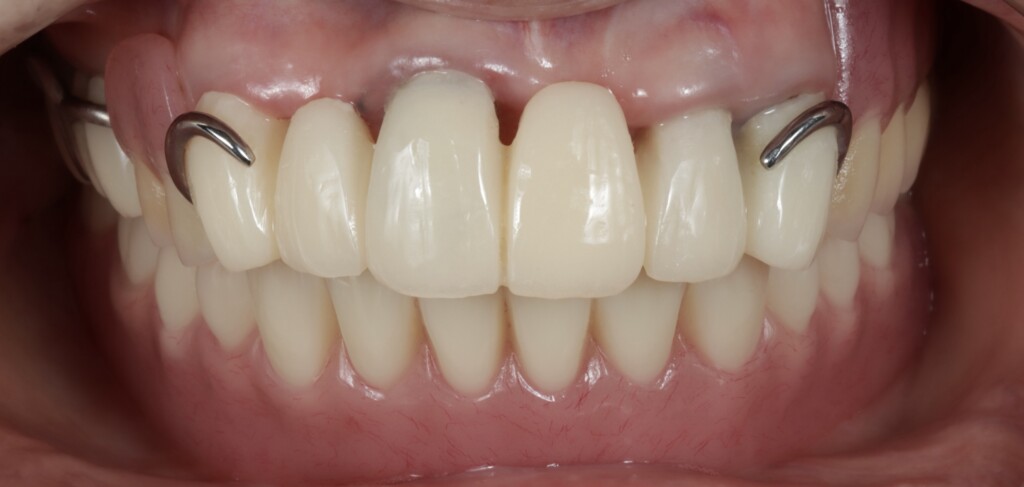

装着された仮歯と仮の入れ歯

乱れた噛み合わせの平面

修正して整えた噛み合わせの平面

いきなり最終的な歯や入れ歯を作るのではなく、段階的に治療を進めていきました。

まずは仮歯と仮の入れ歯を用いて、乱れていた見た目や噛み合わせの平面を整えました。そのうえで、その状態が実際にお口の中で無理なく機能するか、違和感なく順応できるかを確認し、残っている歯の状態を評価しました。さらに、ブリッジやクラウンによる修復が可能かどうかについても、慎重に判断を行いました。残っている歯はいずれも神経の処置がされている歯でしたが、根管内の状態に問題が認められたため、再度根管治療を行っています。具体的には、仮歯を外して根管治療を行い、治療後に土台を立て、再び仮歯を仮止めで装着する、という工程を繰り返し行いました。

上顎の残っている歯は、これまでブリッジや被せもので連結されていたため分かりにくい状態でしたが、詳しく評価を行ったところ、左上の犬歯(糸切り歯)を除き、いずれの歯にも動揺が認められました。また、骨に埋まっている部分(支持組織)も少なく、歯を支える力が低下している状態でした。この点については、治療開始前の検査の段階である程度予測はできていましたが、実際には歯ぐきより上に十分な健全歯質も残っていない状況でした。このような歯に対して、ブリッジやクラウンのように歯へ大きな負担がかかる治療方法を選択し、さらに部分入れ歯の留め金をかける設計とした場合、負担が集中し、状態の悪化を招く可能性があります。そのため今回は、支える力が低下している歯への負担をできる限り抑える設計として、磁性アタッチメントを用いた入れ歯をご提案しました。

磁性アタッチメントが装着された状態(上顎)

仮歯と仮入れ歯を修理して作った磁石で安定する仮入れ歯